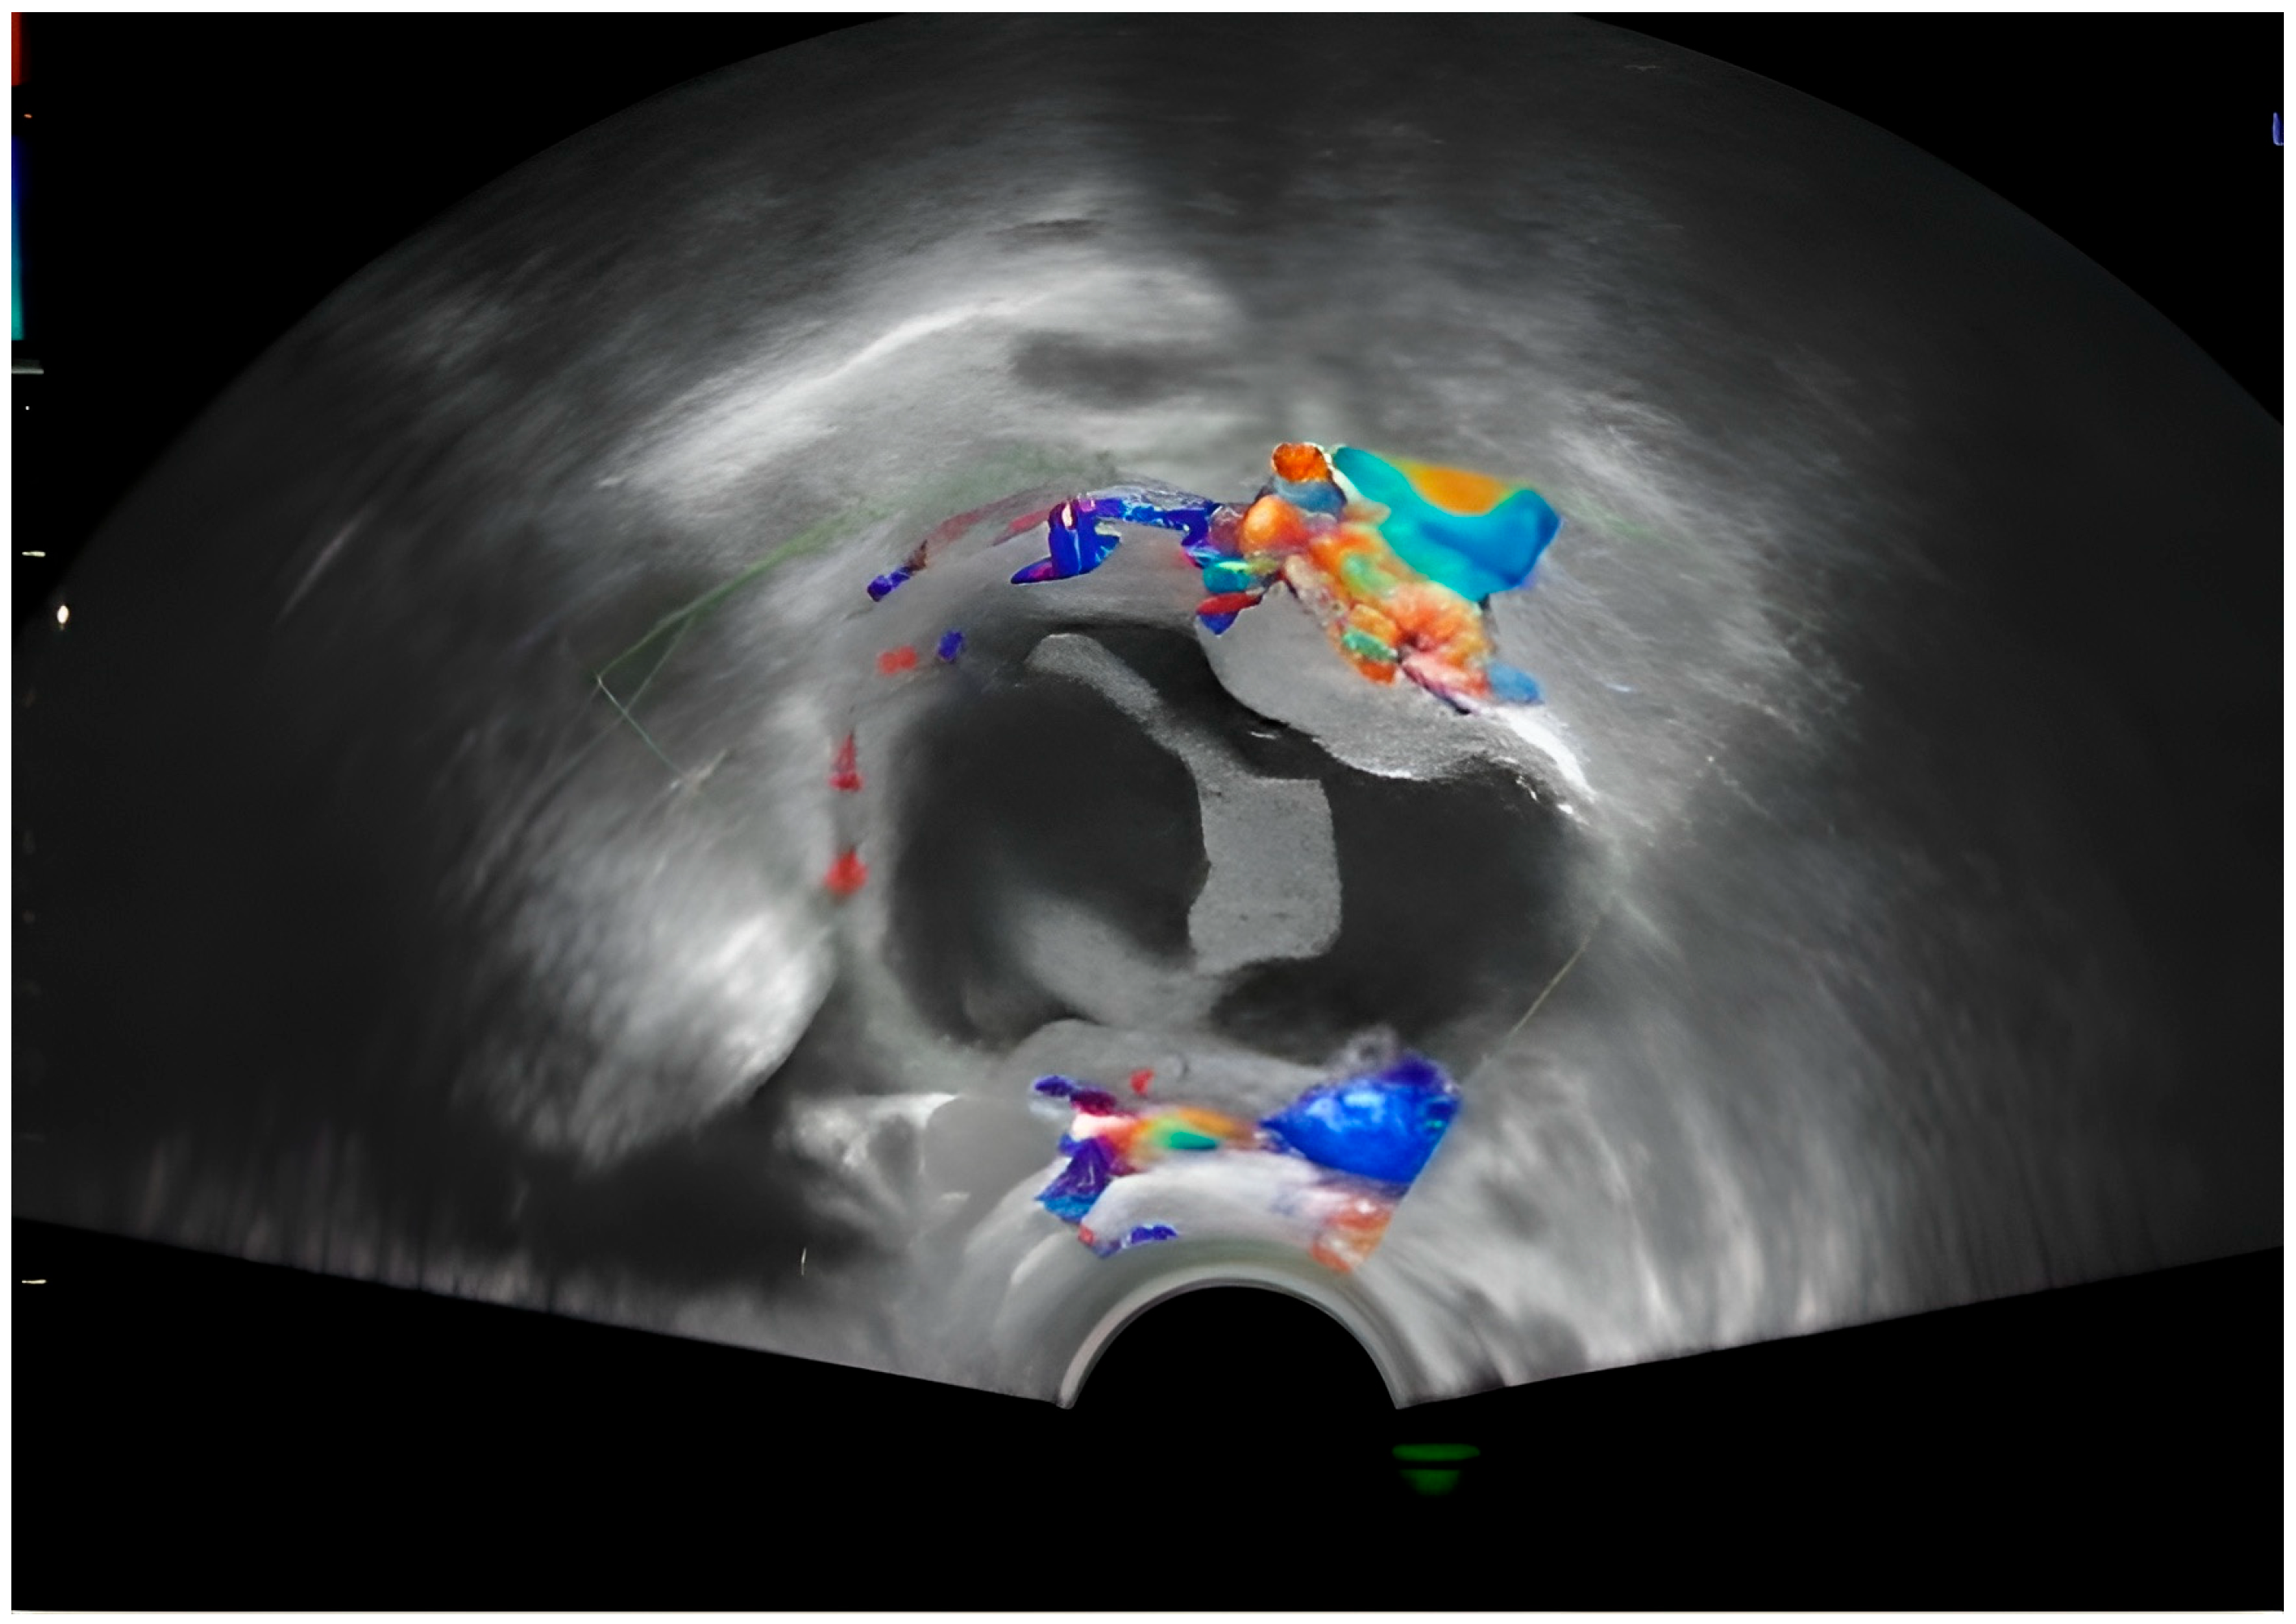

Approximately 3 weeks later, the patient performed a routine check-up with the attending physician, during which the following aspects were detected by ultrasound: Pregnancy 16 weeks and 2 days in progress; on the right laterouterine site an image of about 5 cm is visualized, with regular contour, mixed content, multiple intracystic vegetations, of which the largest was 3.4/3.2 cm, with Doppler signal present and several small vegetations of approximately 0.2 cm; on the left laterouterine site—an image of 3/1.8 cm, with regular contour, intracystic vegetation and Doppler signal; no free intraperitoneal fluid was detected. Following this ultrasound, the suspicion of ovarian neoplasm was raised and the patient was advised to undergo more advanced imaging investigations (Figure 2).

The central structure appears anechoic to hypoechoic, indicating that it is filled with fluid. The internal appearance of the cyst seems to have some irregularity or septation, which may suggest a complex cyst. The red and blue signals in the walls or septa show vascularization. This Doppler scan helps to assess blood flow. In this image, peripheral flow is visible (Figure 2).

Figure 2. Transvaginal pelvic ultrasound with Doppler examination showing (seen as blue and red) a right adnexal growth with a mixed hypo-hyperechoic component and the presence of a peripheral Doppler signal, suggestive of a complex mass lesion.